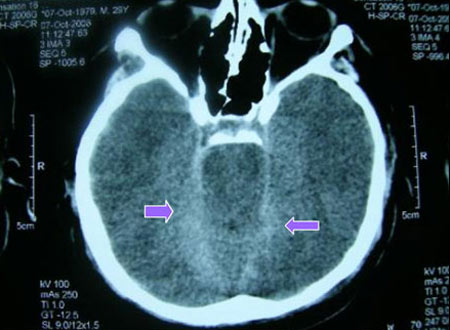

CEVAP: Glioblastome genellikle ameliyatla tam olarak çıkarılamayan tümörler grubuna girer. İlk tedavi ameliyattır. Sonra hastanın durumuna göre radyoterapi ve kemoterapi birlikte uygulanabilir. Radyoterapi bittikten sonra en az 6 ay daha kemoterapiye devam edilir. Glioblastome multiforme’de son 7-8 yıldır kullanılan bir kemoterapi ilacı hastalarda yaşam süresi ve kalitesini artırdı. Eğer tedaviye rağmen nüks olursa başka bir kemoterapi ilacına geçilir. Aşı tedavisi henüz araştırma safhasında, rutin uygulanan tedaviler araşma girmedi. Tamamlayıcı tıp konusuna gelince…